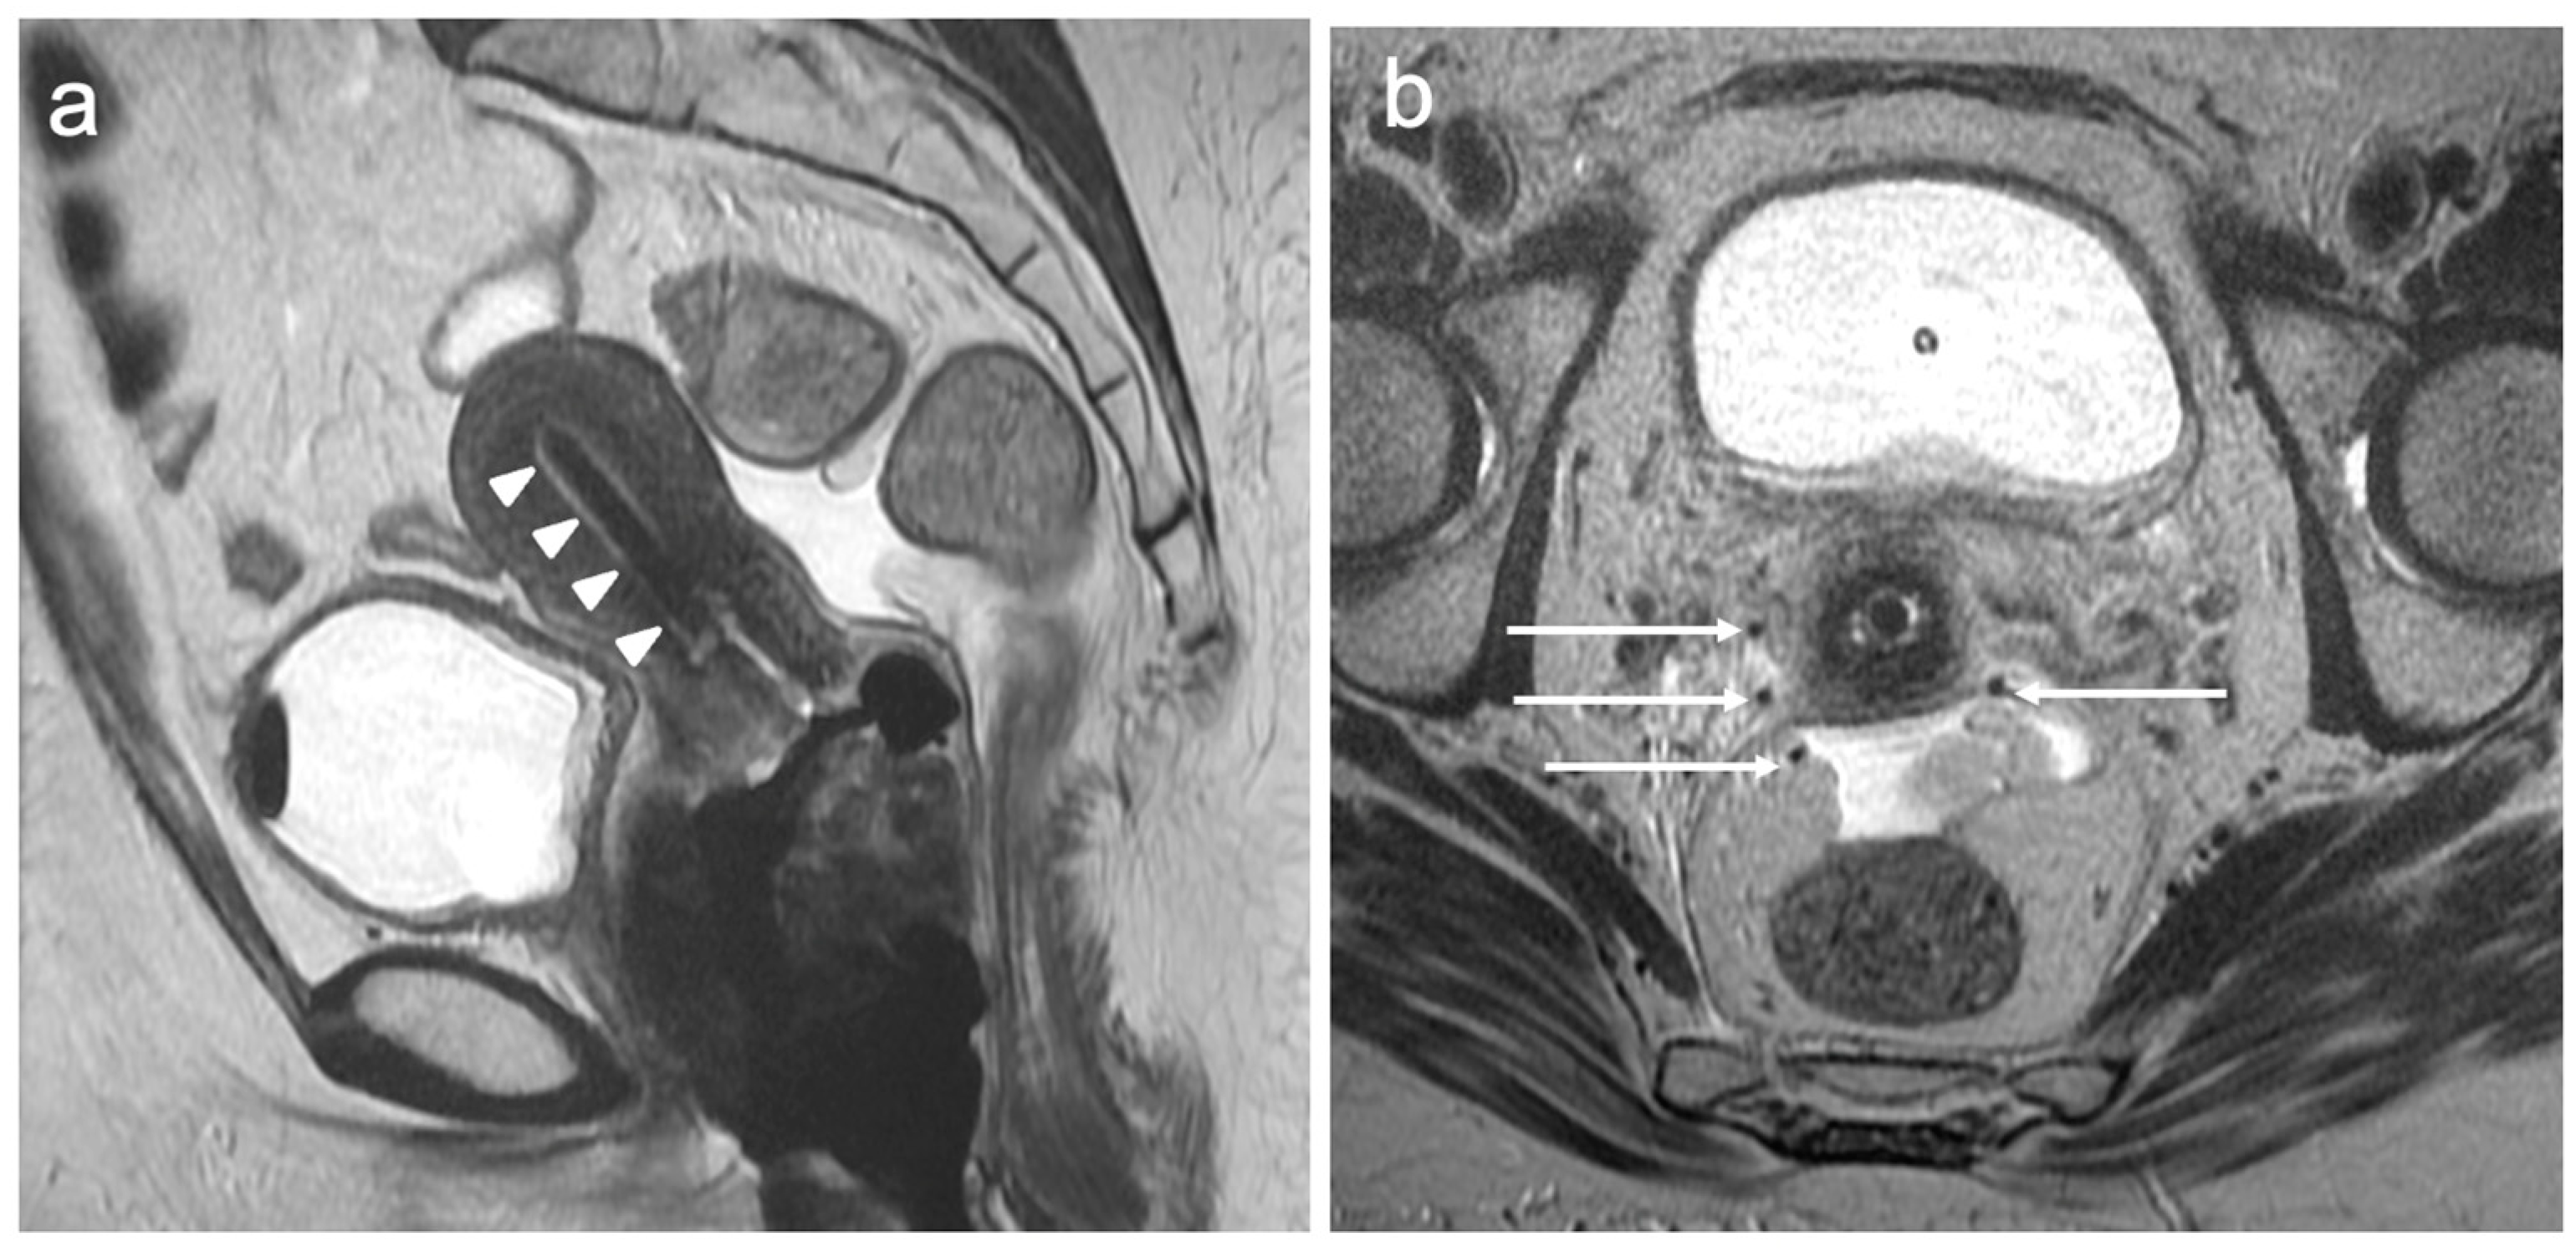

| Stage III | Involves the lower third of the vagina and/or extends to the pelvic wall and/or causes hydronephrosis or non-functioning kidney and/or involves pelvic and/or paraaortic lymph nodes |

| IIIA | Involves lower third of the vagina, with no extension to the pelvic wall |

| IIIB | Extension to the pelvic wall and/or hydronephrosis or non-functioning kidney (unless known to be due to another cause) |

| IIIC | Involvement of pelvic and/or paraaortic lymph nodes |

| IIIC1 | Pelvic lymph node metastasis only |

| IIIC2 | Paraaortic lymph node metastasis |